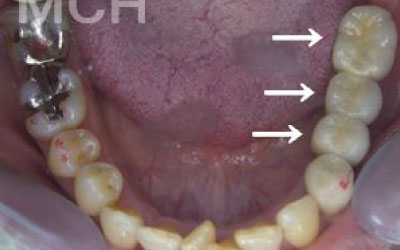

お口の状態や噛み合わせによって異なるため、一概には言えませんが、基本的には奥歯、特に一番奥とその手前の大臼歯部分がおすすめです。

噛み合わせの力の約60%以上がこの奥の二本の歯で支えられているため、ここをインプラントでしっかり治療することが非常に効果的です。

2 歯が傾いてくる、落ちてくる

歯はお互いに支え合ってバランスを取っています。ですので、歯が抜けるとその支えがなくなり、抜けた部分の隣の歯が倒れたり、上の歯が下に下がってくることがあります。